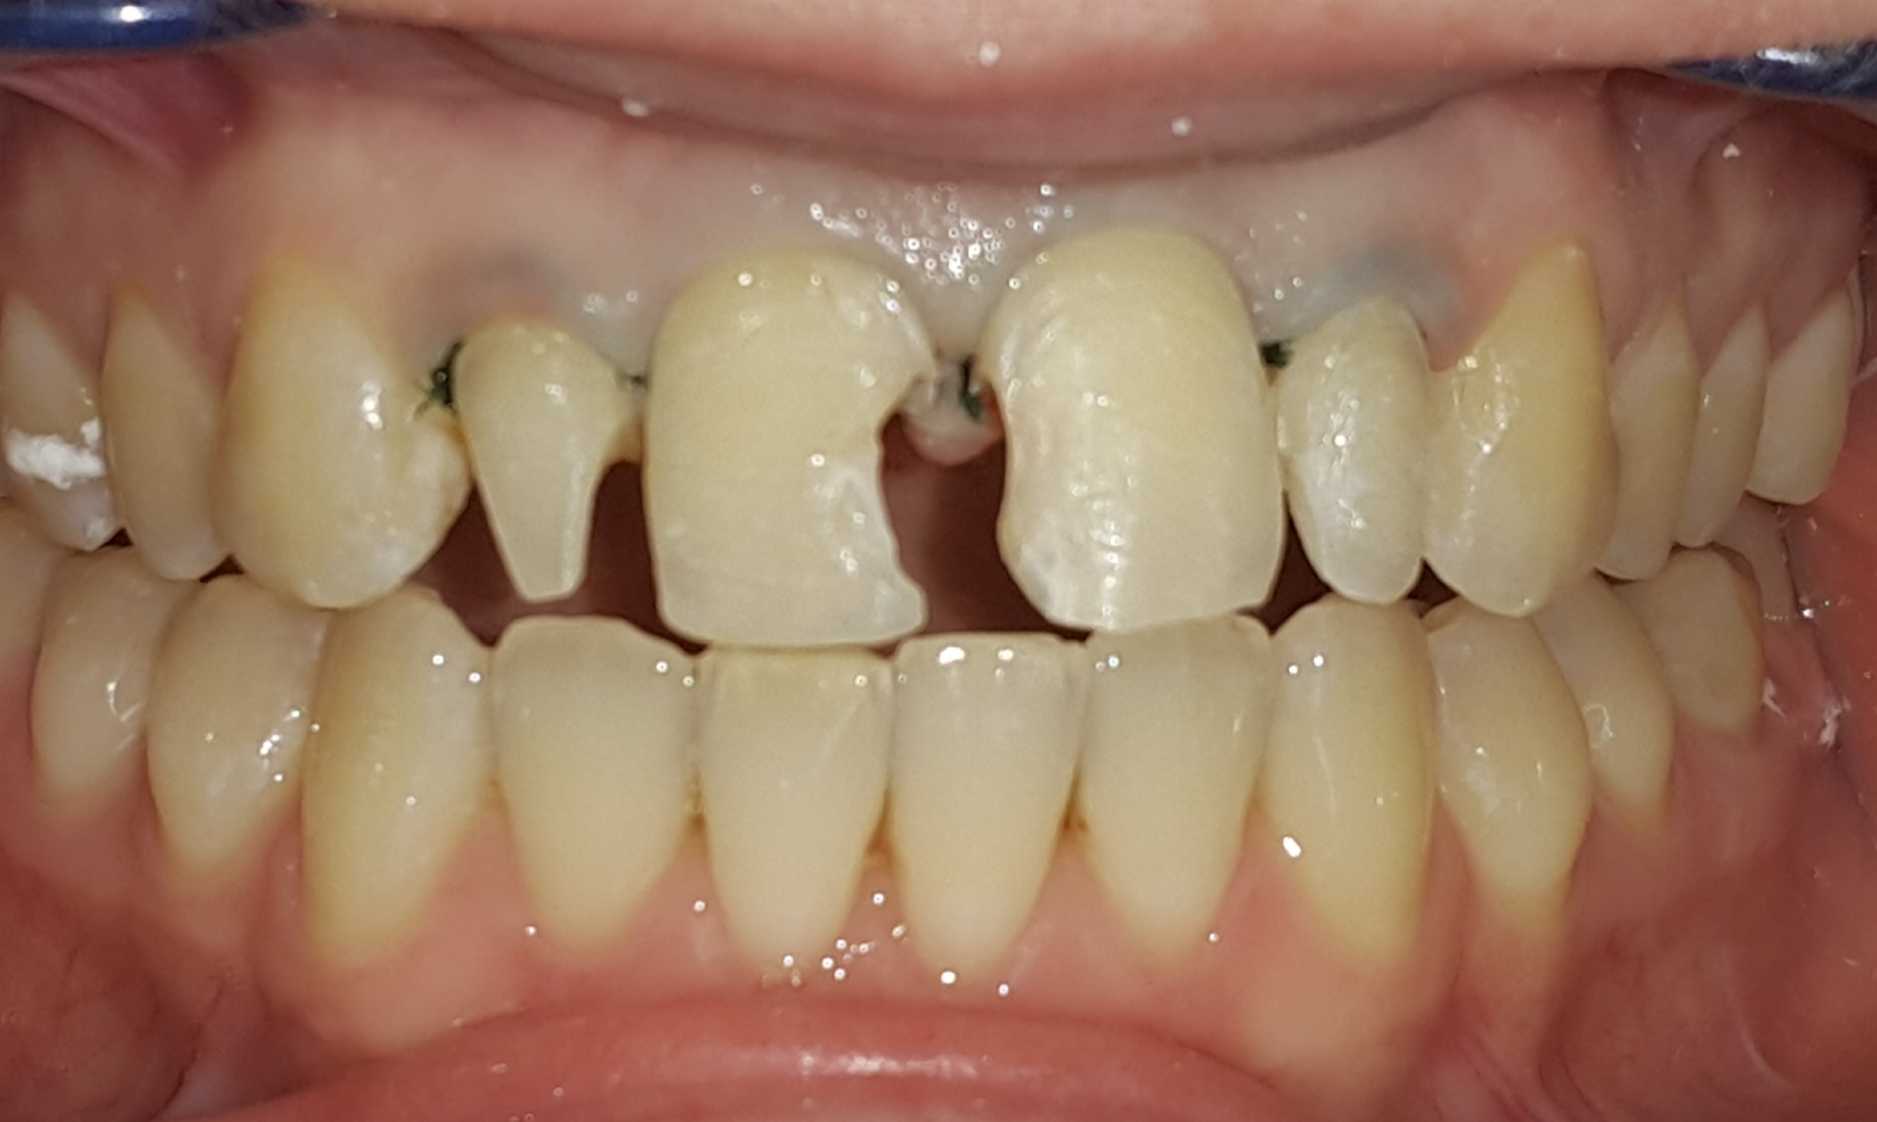

Лечение корневых каналов зуба 3.7. Стрелкой на первом фото указан размер очага воспаления костной ткани. Второй снимок-контроль пломбирования каналов. Третий снимок- активное заживление очага (компьютерная томография через 5 месяцев).